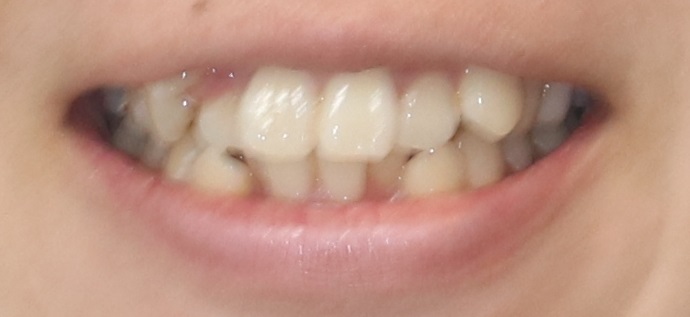

1矯正・マウスピース【治療例1】

治療前

治療後